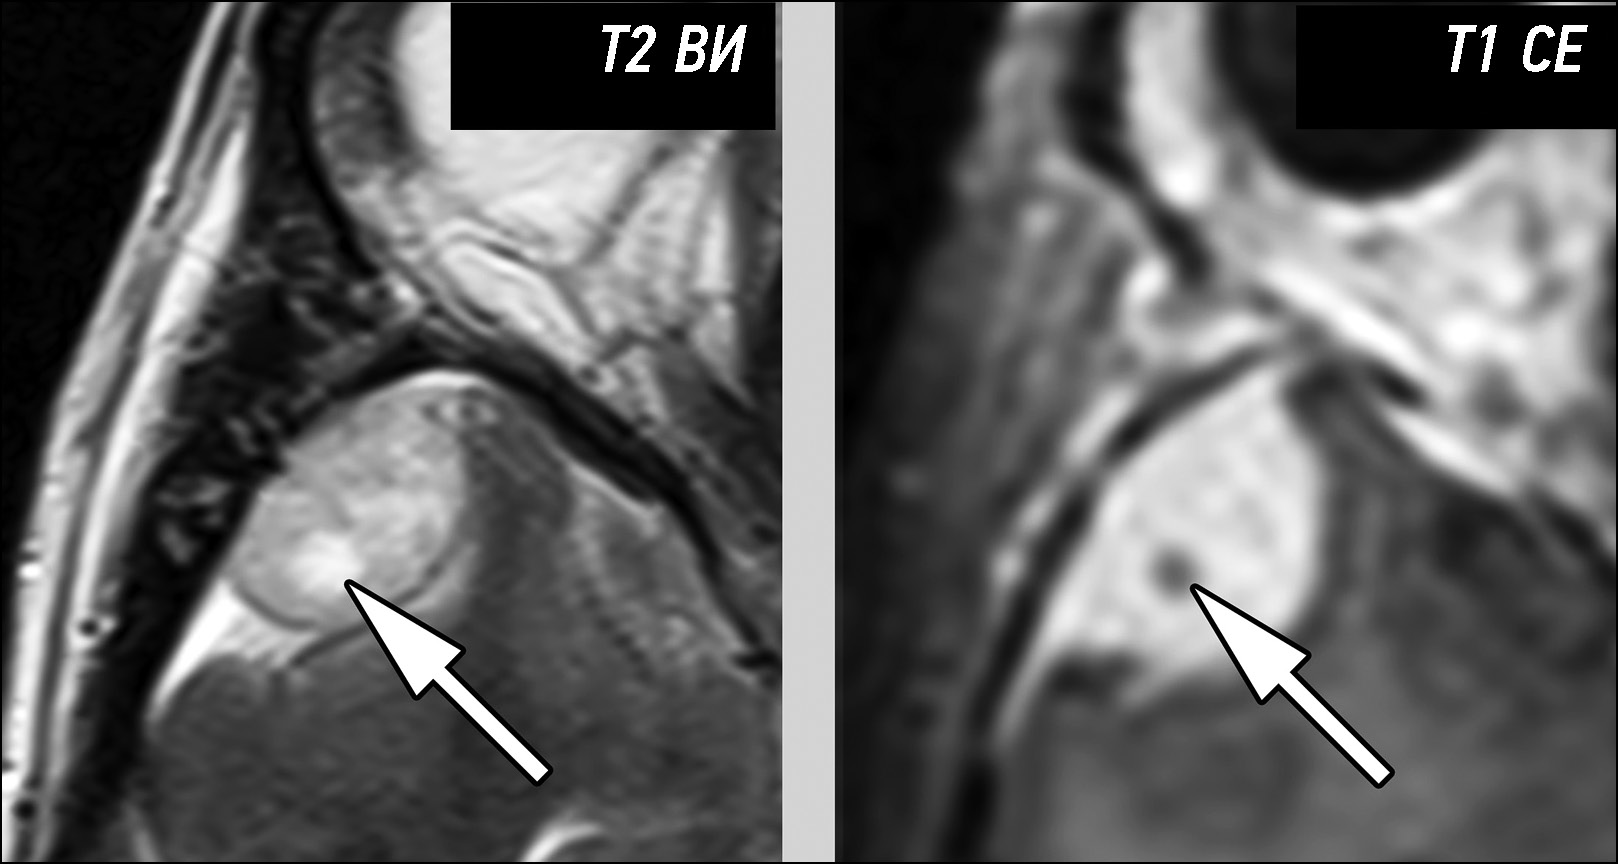

Инструментальная диагностика. На МРТ-изображениях (рис. 3) в правом мостомозжечковом углу определяется чётко отграниченное образование с ровными чёткими контурами, размерами 2,4×1,4×1,8 см. Структура опухоли однородная, но контрастирование невыраженное (преимущественно периферическое) и гетерогенное.

Рис. 3. Гетерогенность контрастирования доброкачественной менингиомы. В ряде случаев доброкачественные менингиомы невыраженно и неоднородно повышают свои сигнальные характеристики после контрастирования (стрелка).

Дифференциальная диагностика. Внемозговые опухоли мостомозжечковых углов необходимо дифференцировать между менингиомами различной степени злокачественности и невриномами.

Отсутствие чёткой взаимосвязи с черепными нервами стало основанием для исключения невриномы из дифференциального ряда.

Чёткость контуров и однородность структуры характерны для доброкачественных опухолей. В то же время неоднородность контрастирования типична для злокачественных менингиом. Характер контрастирования опухоли послужил основанием для ошибочной диагностики, выявленное образование было диагностировано как атипичная (Grade 2) менингиома.

Лечение. Пациенту выполнена резекция опухоли, гистологическое заключение: менингиома (Grade 1), С70.0 9530/01.

Инструментальная диагностика. На серии МРТ-изображений (рис. 5) в эпифизарной области визуализировано внемозговое образование однородной структуры и контрастирования, размерами 2,9×2,6×2,5 см. Опухоль деформирует пластинку четверохолмия, суживается просвет водопровода мозга без развития окклюзионной гидроцефалии.

Рис. 5. Нетипичные проявления злокачественной менингиомы на магнитно-резонансной томографии: a — Т2-ВИ; b — Т1-ВИ; c — Т1-CE. Представлена злокачественная менингиома (*), расположенная в эпифизарной области. Определяется инвазия опухоли в валик мозолистого тела (стрелка).

Граница между новообразованием и валиком мозолистого тела на небольшом протяжении не прослеживается, но отёка вещества мозга в данной области не определяется.

Дифференциальная диагностика. Однородная структура и гомогенное контрастирование послужили решающими факторами для ошибочного отнесения выявленного образования к доброкачественным менингиомам. Вероятно, из-за их наличия рентгенолог не обратил внимания на наличие небольшого участка инвазии опухоли в вещество мозга (валик мозолистого тела).

Лечение. Пациентке выполнена резекция опухоли, гистологическое заключение: атипичная (Grade 2) менингиома, С70.0 9539/32.